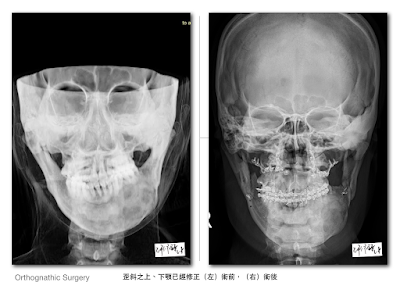

牙齒藉由齒顎矯正醫師的妙手排列整齊了,但骨頭及顏面的歪斜需要外科的介入才能改善。婷婷的臨床症狀比較複雜,治療需同時合併腫瘤切除及正顎手術,因此雖然求助過幾位外科醫師,卻都沒有得到妥善的協助。

為求慎重,我再一次替婷婷做了病理切片,安排電腦斷層檢查並運用3D影像技術進行手術模擬。經過審慎評估後,我有自信能幫助婷婷再拾往日笑容。